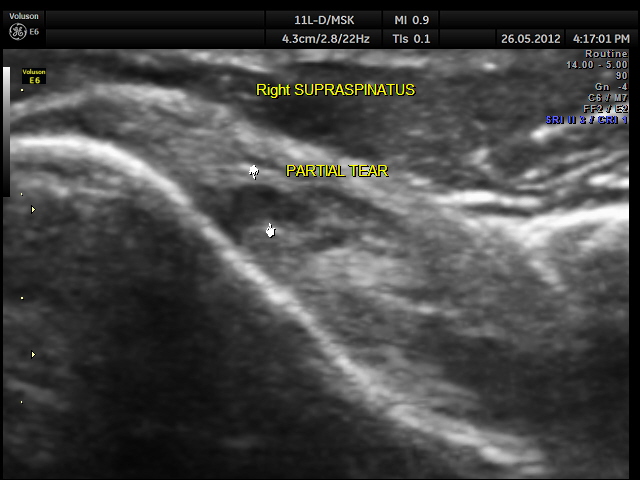

SUPRASPINATUS TEAR Date: May 27, 2012Author: kriznan Category: Shoulder, Musculo-skeletal ultrasound Tags: MUSCULO SKELETAL ULTRASOUND, PARTIAL TEAR, SHOULDER ULTRASOUND, SUPRASPINATUS TEAR Post navigation ← NON IMMUNE HYDROPS VESICAL CALCULI → This slideshow requires JavaScript.For imaging the rotator cuff, we need the high resolution transducer and appropriate positioning ; for the supraspinatus , I prefer the patient keeping his hand (of the side of the shoulder being examined ) in the opposite back pocket position Share this: Share on X (Opens in new window) X Share on Facebook (Opens in new window) Facebook Email a link to a friend (Opens in new window) Email Share on LinkedIn (Opens in new window) LinkedIn Share on WhatsApp (Opens in new window) WhatsApp More Print (Opens in new window) Print Share on Reddit (Opens in new window) Reddit Share on Tumblr (Opens in new window) Tumblr Share on Pinterest (Opens in new window) Pinterest Share on Telegram (Opens in new window) Telegram Like Loading...